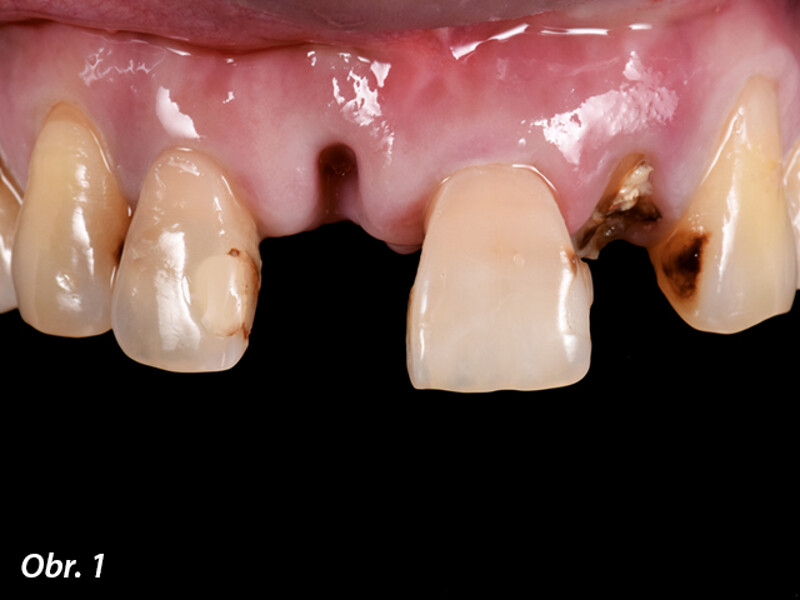

Okamžitá implantace a CADCAM